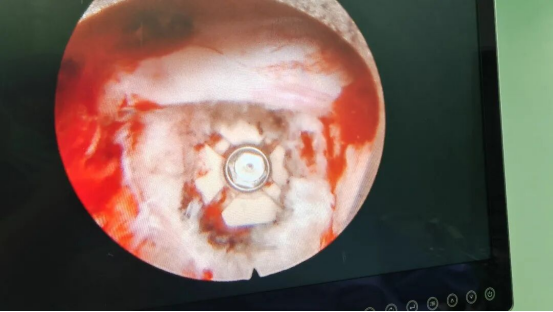

术中镜下置入融合器